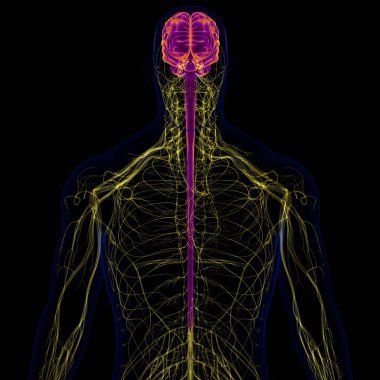

Tıbbi Konsept için sinir sistemi anatomisi olan 3D İnsan Beyni

MaviGrafikselresimlemeŞeffafİnsanSağlıkBaşıİlaçerkekkordonüç boyutlubiyolojikHücregövdeHastalıkİstihbaratİçeridebiyolojiBilimSistemAcıorgzihinomurgaelektronİşaretgörüntü oluşturmaanatomiomurilikbeyinMerkezGerginNörolojimikroskobikBeyin fırtınasıSıhhiyeanatomikSinirbeyincikcerebra3d oluşturmaüzerine siyahsinir hücresiBenzer İçerikler